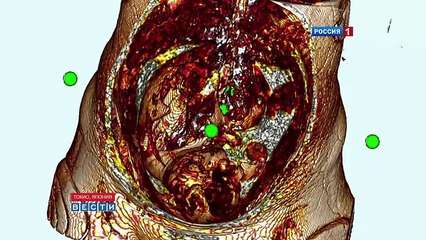

Echographie Souvenir 3D 4D chez Baby Live Montpellier